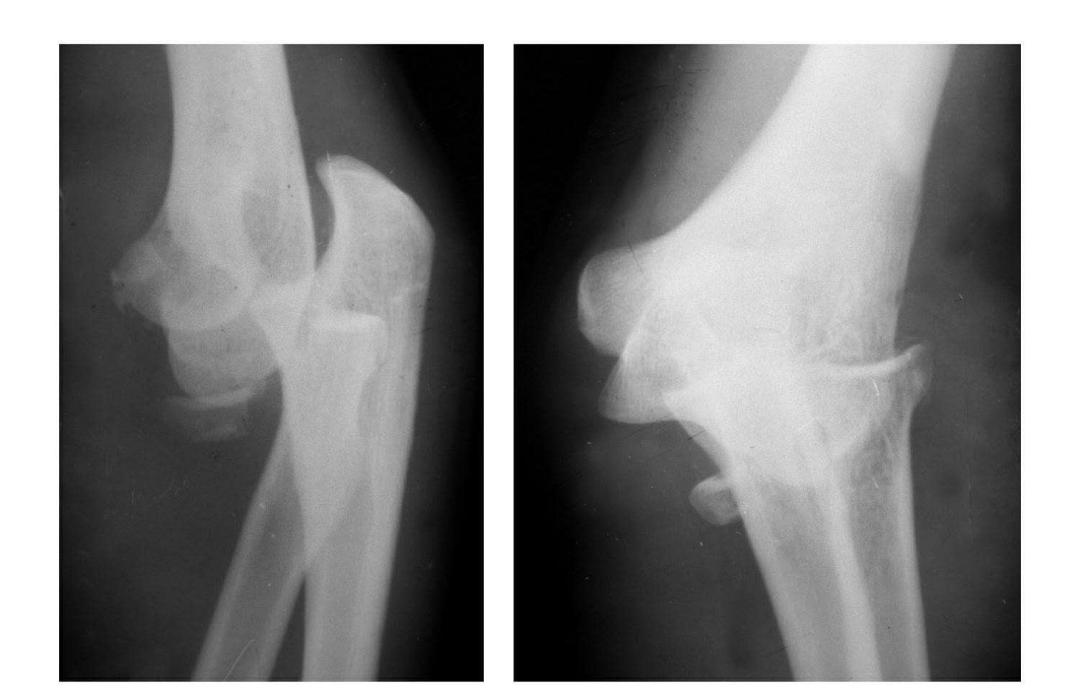

例3:肱骨小头及滑车桡侧壁前半部呈整体性冠状面骨折,骨折块向前上移位并外髁骨折。

(二)部分骨折

本病亦称科-洛(Kocher-Lorenz)型骨折

例1:肱骨小头软骨面及其下方少量骨质呈“新月样”被剥脱,且向肘前上方移位并桡骨头前半部骨折。

例2:肱骨小头软骨面剥脱性骨折,致该小头新月状骨片被向前脱位的桡骨头顶向肘关节前上方,并尺骨干中段骨折(孟氏伸展型骨折)。